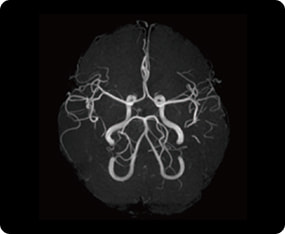

頭部MRI検査の症例画像

血管(MRA)